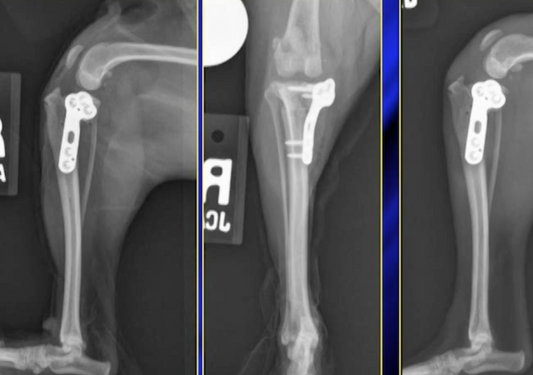

Mes genoux me tuent - la gestion de l'insuffisance de ligament Cruciate crânienne

Les Cibles en mouvement - Guide de Survie à Patellaire Médial Luxation